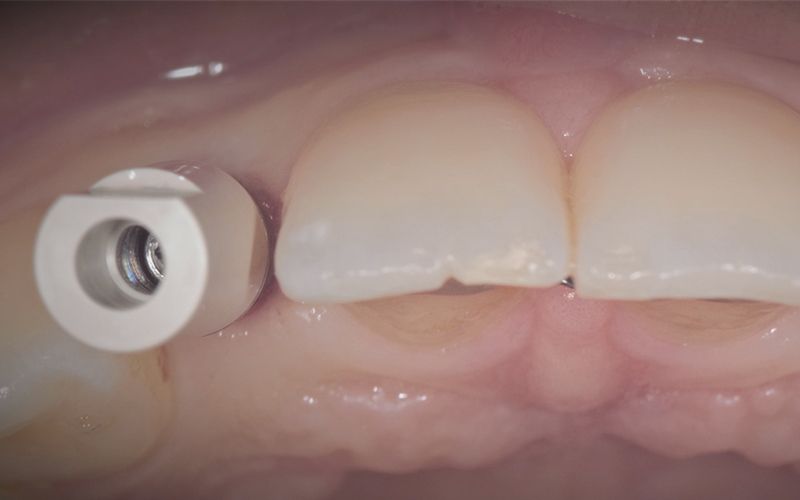

Se llevó a cabo la cirugía de colocación simultanea de los implantes Pearl de 2.8 x 13 mm en posición de 12 y 22 siguiendo el protocolo indicado por la casa comercial. Estos fueron colocados con éxito a pesar de que las condiciones anatómicas no eran muy ventajosas, consiguiendo 30 Ncm de torque en ambos.

Tras tres meses de osteointegración, se procedió a realizar la segunda cirugía de ambos implantes y se tomaron las impresiones digitales con el escáner intraoral TRIOS (3Shape).

Las coronas de zirconio monolítico fresado con cut-back iban cementadas sobre dos bases de titanio previamente talladas para salvar el eje de inserción de los implantes.